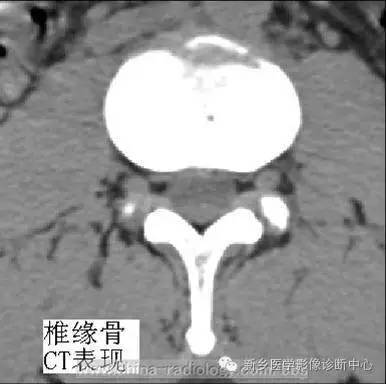

CT表现病变椎体后缘骨质缺损区,多位类圆形或分叶状,大小不一,与同层椎间盘密度相等,CT值为65~90HU,边缘清楚,常有厚薄不一的硬化带,骨质缺损区后方均可见条状或弧状骨块突入椎管内,骨块多与椎体一侧相连,少数两侧与椎体完全分离,可致椎管狭窄、硬膜囊受压。当病变椎体后缘增生硬化非凡明显时,椎体后缘骨质缺损情况需仔细辨认并结合MRI检查以明确诊断。

(4)椎体后缘骨质增生,多见于老年患者,多出现于椎体前缘及侧缘,与椎体紧密相连,密度较高,高密度中不含软组织密度影。CT特点为椎体周缘不规则骨块附着于锥体,矢状位重建显示椎体后缘骨赘压迫硬膜囊。